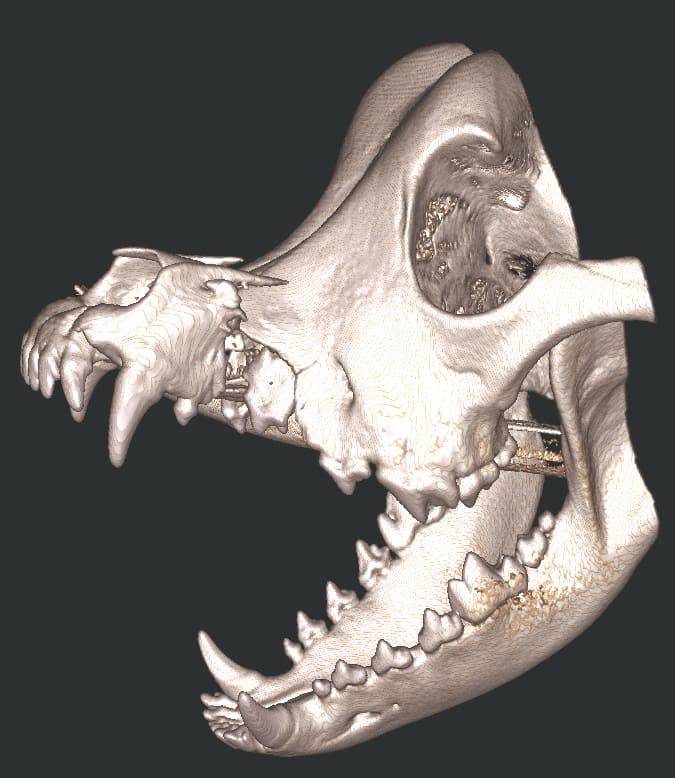

The Center now provides advanced imaging via cone beam CT. Cone beam CT is excellent for visualization of bony structures of the skull, nasal cavity, teeth, and ears. Cone beam CT is especially helpful for diagnosing dental disease and evaluation of jaw fractures. It can also be useful for evaluating the sinuses and tympanic bulla. Cone beam CT can be used in conjunction with nasal biopsy and culture to evaluate nasal discharge whether chronic or acute.

Pets can be involved in trauma that can cause fractures to their head, teeth, and jaw bones. Correctly repairing these fractures is extremely important for your pet to have normal function of their mouth. If a jaw fracture is allowed to heal in an abnormal position, your pet may have great difficulty chewing and can be in significant pain. Many fractures can be successfully treated with minimally invasive oral procedures, but more complicated cases may require bone plating techniques. The Center offers cone beam CT imaging which provides extremely detailed images of the bones of the head and skull. Advanced imaging with CBCT facilitates selection of the best surgical technique to get your pet back to eating and comfort as soon as possible.